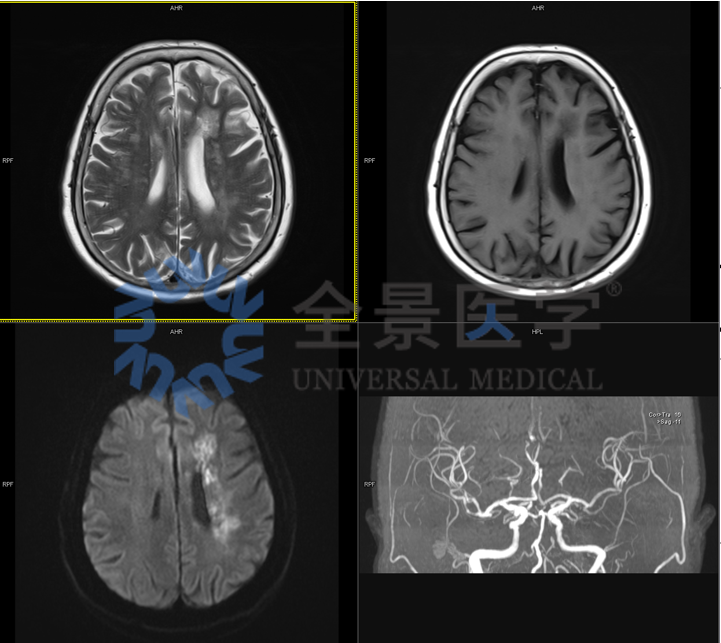

70 岁,女性,记忆力下降 1 年,糖尿病、高血压、高血脂 20 年余。

MRI 及 MRA 显示:

①左侧半卵圆中心‐放射冠、侧脑室周围新近脑梗塞;②老年脑,多发脑白质变性;双侧基底节区 VR 间隙;③右侧后交通动脉瘤;脑动脉硬化并多发轻‐中度狭窄。